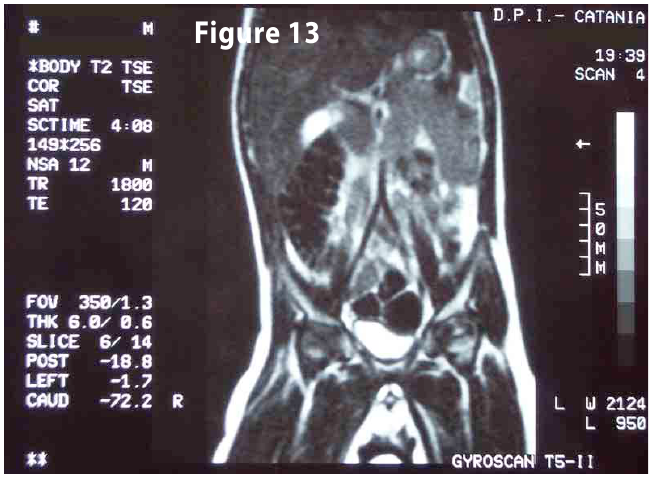

Figure13